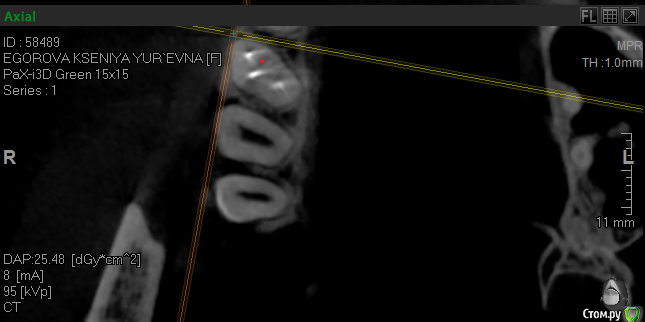

krokomot Опубликовано 17 октября, 2019 Поделиться Опубликовано 17 октября, 2019 Проблема в фуркации шёчных каналов, есть расширение щели и сниженный показатель денситометрии кости прилегающей к этому участку, в отличие от других участков, это означает что кость там находится в процессе атрофии. Ссылка на комментарий

vse32 Опубликовано 18 октября, 2019 Автор Поделиться Опубликовано 18 октября, 2019 Проблема в фуркации шёчных каналов, есть расширение щели и сниженный показатель денситометрии кости прилегающей к этому участку, в отличие от других участков, это означает что кость там находится в процессе атрофии.Самая привлекательная для меня версия. Считаете проблема в бифуркации? Ссылка на комментарий

krokomot Опубликовано 18 октября, 2019 Поделиться Опубликовано 18 октября, 2019 По кт пломбировку каналов и состояние корней судить нельзя, только опосредовано через состояние периодонтальной щели и костной ткани, это относительно достоверные признаки, при трещине или переломе мы не увидим трещину корня, но увидим измененя косиной ткани. В данной ситуации по кт сомнительную зону я обнаруживаю только в области фуркации щечных каналов, и то я вления не выраженные, хотя длительный процесс более месяца обязан был дать четкую картину на кт, но ее нет. Была у меня такая пациентка с периодонтитом переднего зуба, болел полгода, никаких рентегологических признаков указывающих на периодонтит небыло, вскрытие показало канал пустой. Ссылка на комментарий

___49___ Опубликовано 18 октября, 2019 Поделиться Опубликовано 18 октября, 2019 устье плохо визуализируется , больше ориентируюсь на анатомию корня , два скрина с отметкой и без . Ссылка на комментарий

___49___ Опубликовано 18 октября, 2019 Поделиться Опубликовано 18 октября, 2019 еще 2 скрина также с меткой и без , где четко виден канал мб2 Ссылка на комментарий